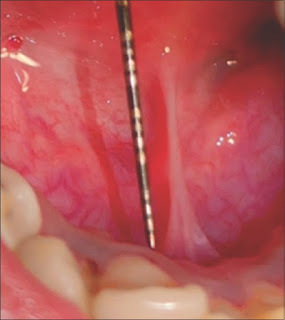

| Release of ankyloglossia using diode laser Akanksha Samvedi, MM Dayakar, Prakash Pai, George Philip, H Shivanand Journal of Dental Lasers 2018 12(2):63-66 Ankyloglossia is defined as a condition in which the tip of the tongue cannot be protruded beyond the lower incisor teeth because of a short lingual frenulum. The prevalence of ankyloglossia is 4.8%. An unusually short lingual frenum results in complications in speech, oral hygiene, lingual recession, etc. To have a healthy lifestyle, treatment becomes necessary. Lingual frenectomy is the treatment of choice. With the advent of lasers, the treatment has become simple, precise, and less discomfort compared to the conventional. The present case report deals with the treatment of ankyloglossia using 980 nm diode laser. |

| Diode laser for lingual frenectomy Soni Bista, Khushbu Adhikari, Charanjeet Singh Saimbi, Bikash Agrahari Journal of Dental Lasers 2018 12(2):74-76 Ankyloglossia or tongue tie is characterized by short lingual frenum restricting tongue movement which causes feeding difficulties and speech problems. Such condition can be treated by frenectomy using scalpel, laser, and electrocautery. The present case reports ankyloglossia in an 11-year-old female patient treated with diode laser and followed up without any complications. |